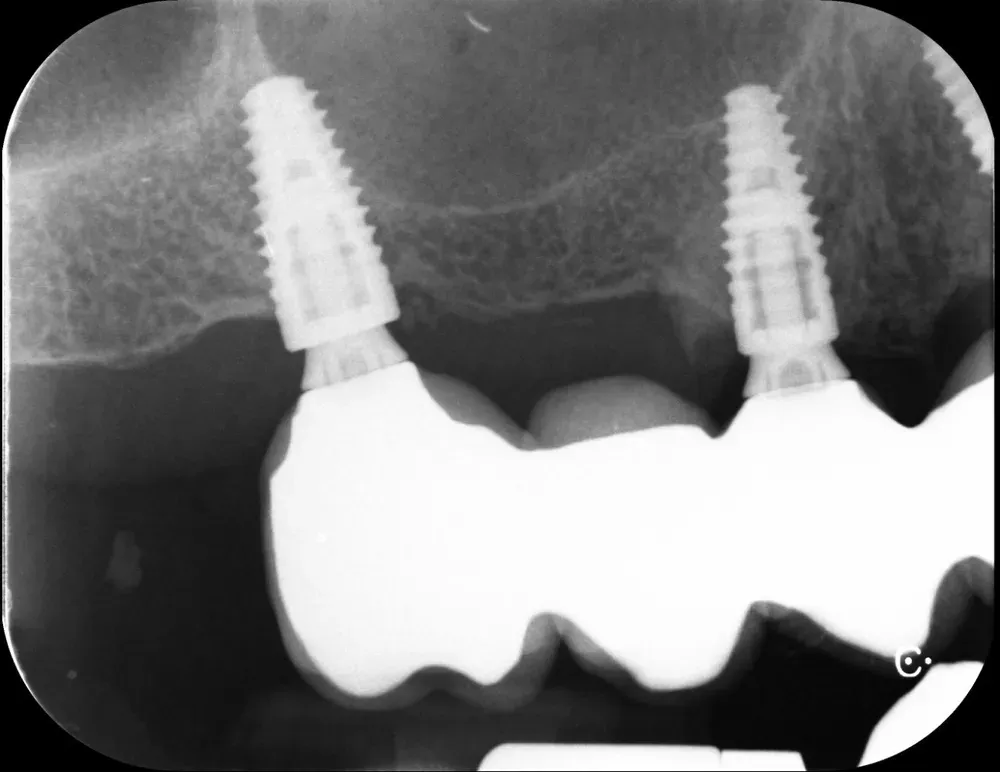

Il mascellare superiore destro era affetto da atrofia categoria S3 CCARD in posizione 16 e S2 CCARD in posizione 14 (precedentemente estratto), con presenza di cisti da ritenzione mucosa e setto di Underwood.

Inserimento impianti con rialzo del seno e aspirazione cisti da ritenzione mucosa del seno mascellare

Ho inserito due impianti, in posizione appunto 16 e 14, con minirialzo del seno mascellare e aspirazione della cisti da ritenzione mucosa tramite accesso laterale.